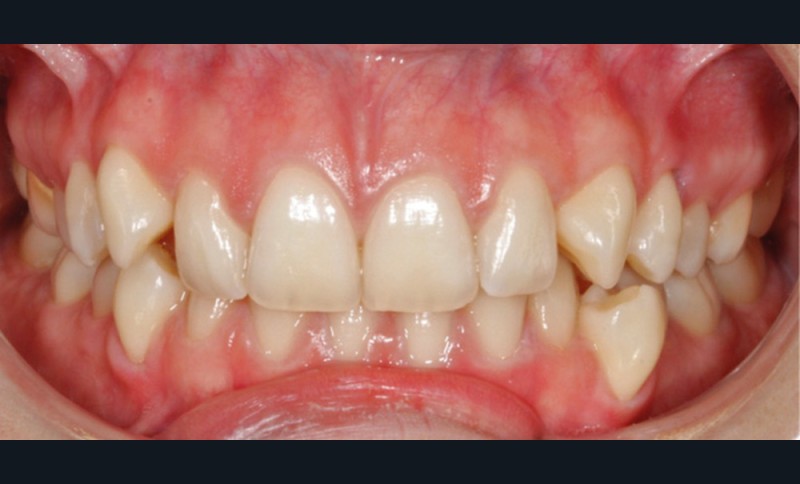

À l’examen exo-buccal, le visage est symétrique, harmonieux et équilibré. La patiente présente une classe I squelettique normodivergente à tendance hypodivergente. Le sourire est perturbé par une visibilité excessive des canines maxillaires, ce qui correspond au motif de consultation.

L’examen intra-arcade met en évidence une hygiène bucco-dentaire irréprochable, favorable à un traitement en technique linguale. Le phénotype parodontal est fin dans la région incisivo-canine mandibulaire. L’encombrement est estimé à 8 mm à la mandibule et à 4 mm au maxillaire (fig. 1). Les arcades ont des formes similaires, en U. Les rapports inter-arcades mettent en évidence une classe 1 d’Angle molaire, une classe 2 d’Angle canine et une supraclusion antérieure (recouvrement : 5 mm ; surplomb diminué). Les milieux inter-incisifs sont déviés entre eux avec une origine mixte (= 1,5 mm) (fig. 2).